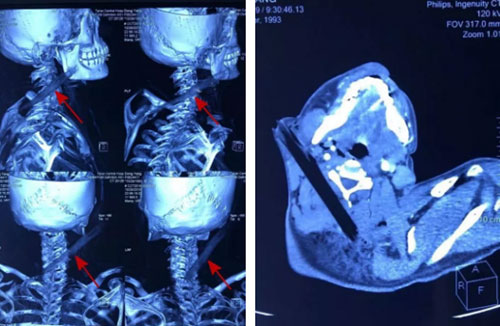

医院耳鼻咽喉头颈外科急诊医师接诊后,迅速检查患者伤情,检查示患者意识可,无呼吸困难、肢体活动障碍、肢体感觉异常,右颈部自耳垂下方插入颈部一不规则木枝样物,颈部无活动性出血,头皮部、胸部多发创伤。急诊医师阅读外院颅脑、颈部、胸部CT示颈部异物自右颈向后下越过脊椎后方至左颈部、颈部血肿、颈部皮下气肿、头皮下血肿、胸骨骨折、上胸部皮下积气、纵膈血肿、创伤性湿肺,请神经外科、血管外科、创伤急诊外科急会诊,认为目前患者无明确颅内出血、脊髓损伤指征,异物与颈部大血管关系不明确,建议行颈部CTA。患者完善颈部CTA显示异物紧靠颈内动脉,必须立即手术。

耳鼻咽喉头颈外科许风雷副主任医师带领团队,在第二麻醉手术科保驾护航下进行急症手术,术中见异物自右颈部插入,经过胸锁乳突肌内侧面,紧靠颈内动脉插入颈后部。树枝表面不光滑,与周围解剖关系复杂,术中仔细分离,取出异物,是一根不规则长柱形木棍,长约15cm手术顺利完成,患者术后很快苏醒,肢体活动正常,颈部活动良好。